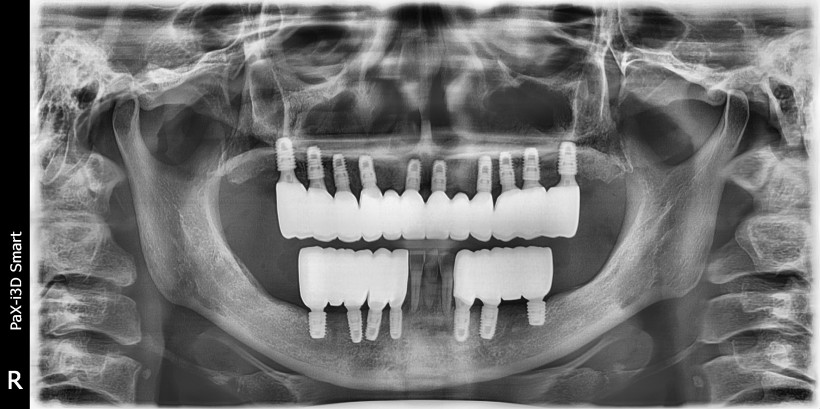

전악 임플란트 치료

치조골 흡수가 심해 임플란트 치료가 힘든 상태에서 전악 임플란트 수복한 케이스